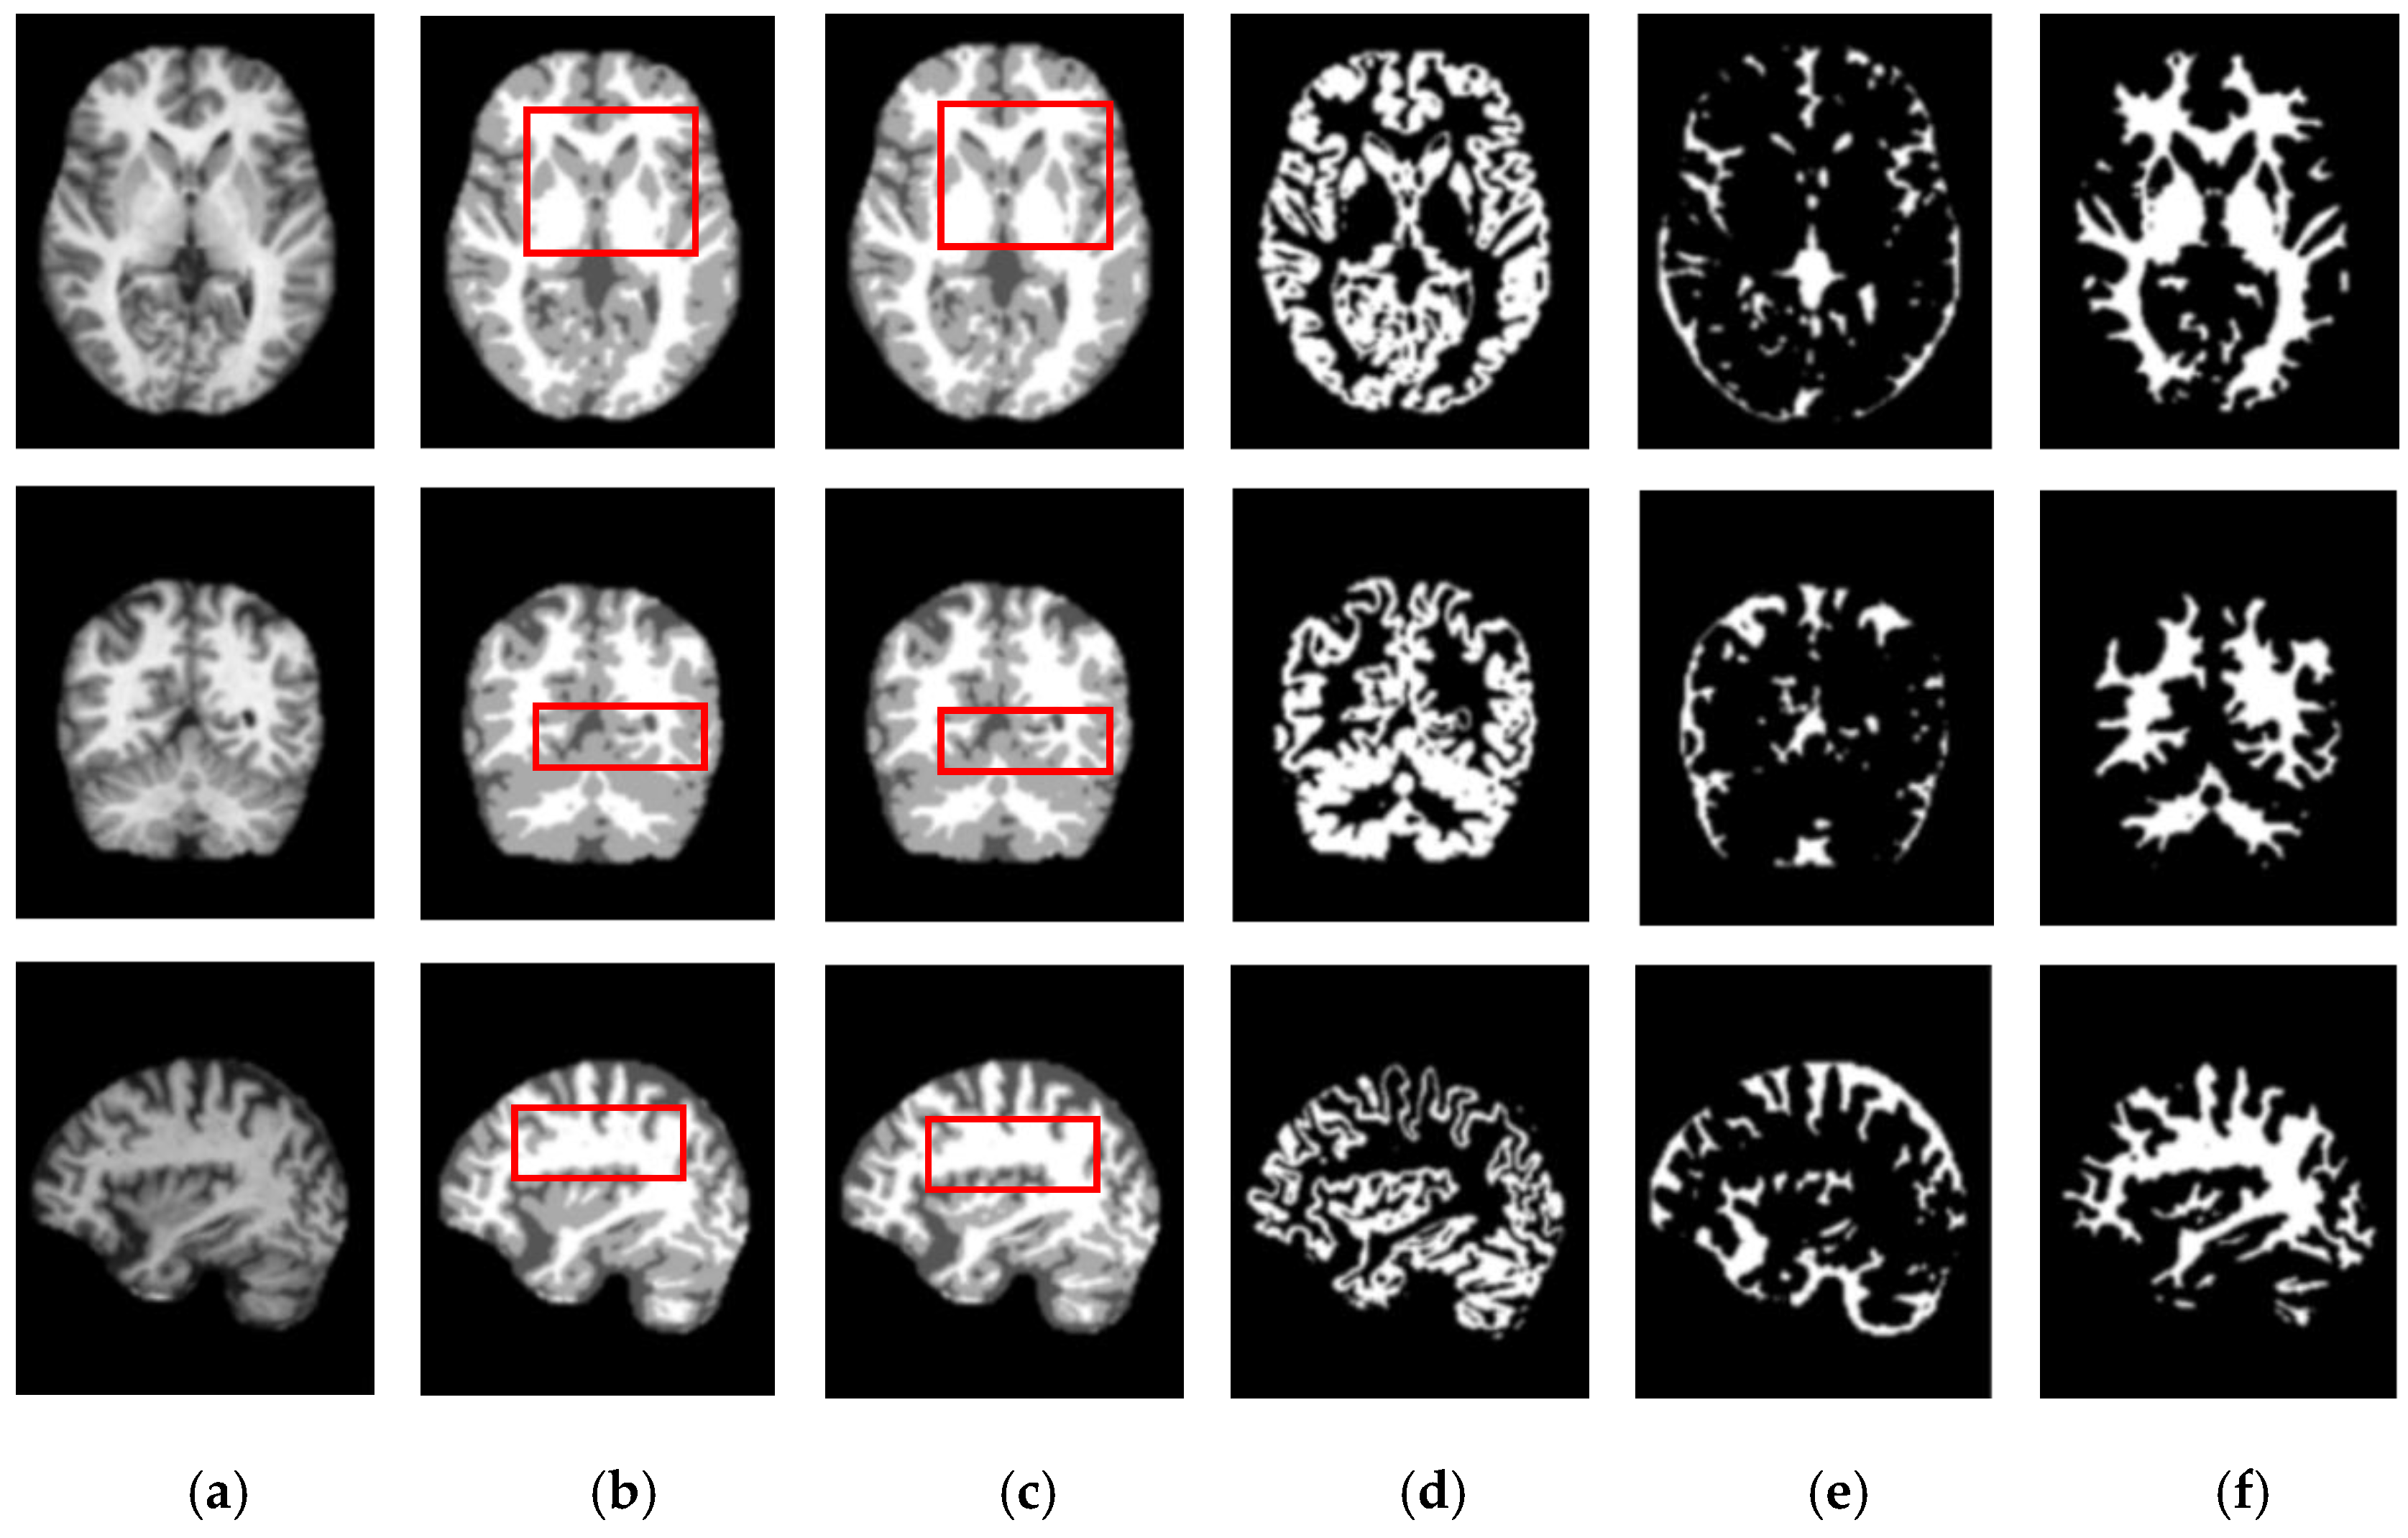

We also assessed the segmentation performance in terms of the mean square error (MSE), which is the average square difference between the original and predicted Y values. The Hausdorff distance (HD) [] was used to determine the dissimilarity between two sets in a metric space. The two sets of small Hausdorff distances are almost identical. HD and MSE are computed as listed in Table 2, where D is the Euclidean distance between two pixels, and R and C are the image height and width, respectively. To compare the segmentation results of various network architectures, we experimented on SegNet, U-net, U-SegNet, U-net++, and CE-net models under the same experimental conditions. Figure 7 and Figure 8 show comparisons of the segmentation results. As shown in Figure 7 and Figure 8, the proposed method shows superior results in terms of the quality of the segmentation map compared to those of other conventional methods. Although the skip connections in the U-net improve feature representations by combining low-level and high-level information, they suffer from a large semantic gap between low- and high-resolution feature maps, resulting in high misclassification rates of brain tissues. Furthermore, for medical images with low contrast, blurred boundaries between different tissues, the segmentation accuracies of U-net and SegNet are significantly degraded. Because the network layers in U-net++ are connected through a series of nested, dense skip pathways, leading to redundant learning of features, they did not show good performance. In particular, it can be observed that there are misclassification results in the feature maps generated by SegNet, U-net, and U-net++ in the red boxes of Figure 7c and Figure 8c. Although U-SegNet with pooling indices and skip connections yields better segmentation results, it fails to capture fine details, as shown in Figure 8c. From the highlighted red boxes in Figure 8, it can be observed that U-SegNet fails to identify differences between WM and GM tissues, and most of the GM tissues are incorrectly predicted as WM. The CE-net extracts multi-scale information through a context encoder block for the segmentation of medical images. However, the context encoder block is employed only at the bottleneck layer of the model, and thus this multi-scale information could be irrelevant by the time it reaches the final decoder layer for classification. To overcome these limitations, we extract multi-scale information at each network layer followed by the GAM to enhance the segmentation performance by directing attention to related areas. This improved segmentation can be observed in the results obtained using the proposed method. Similar results were observed for the segmentations obtained from the IBSR images, as shown in Figure 8. It can be observed that the proposed network obtains finer details than the other architectures. These results indicate that our proposed approach can strongly recover finer segmentation details while bypassing distractions between tissue boundary regions.

Figure 7.

Segmentation results for GM, CSF, and WM from brain MRI image using the existing methods and the proposed method on OASIS dataset: (a) original input image; (b) ground-truth segmentation map; (c) their segmentation results obtained SegNet, U-net, U-SegNet, U-net++,CE-net, and the proposed method (top to bottom); (d) CSF maps obtained by SegNet, U-net, U-SegNet, U-net++,CE-net, and the proposed method (top to bottom); (e) GM maps obtained by SegNet, U-net, U-SegNet, U-net++,CE-net, and the proposed method (top to bottom); (f) WM maps obtained by SegNet, U-net, U-SegNet, U-net++,CE-net, and the proposed method (top to bottom).